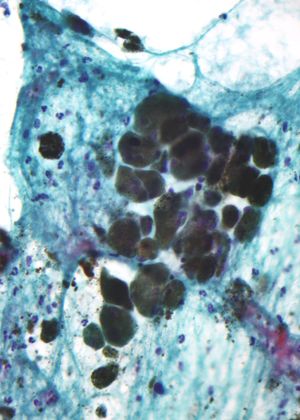

استمع) (باليونانية: μέλας - melas، "أسود، داكن"، هو مصطلح واسع يطلق على مجموعة من الصبغات الطبيعية الموجودة في معظم العضيات (العنكبوتيات هي واحدة من المجموعات القليلة التي لا تحتوي على الميلانين). يُنتج الميلانين عن طريق أكسدة الحمض الأميني التيروسين ثم بلمرته. تُنتج الصبغة ضمن مجموعة خاصة من الخلايا تُعرف بالميلانوسيت.

هناك ثلاثة أنواع رئيسية من الميلانين: الإيوميلانين، الفيوميلانين، والنيروميلانين. أكثر أنواع الميلانين شيوعاً هو الإيوميلانين. يوجد نوعان من الإيوميلانين - الإيوميلانين البني والإيوميلانين الأسود. الفيوميلانين عبارة سيتين - يحتوي على وحدات پوليمر البنزوثيازين الأحمر المسئولة بشكل كبير عن لون الشعر الأحمر، وصبغات أخرى. النيروميلانين يوجد في المخ، على الرغم من أن وظيفته لا تزال غامضة.